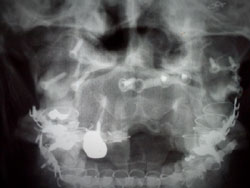

あごの骨はバラバラになりました↓

上あごの骨はなくなり、腰の骨を移植しました↓

バラバラになった頭蓋骨、顔面骨を

ボルトプレートワイヤーで固定 |